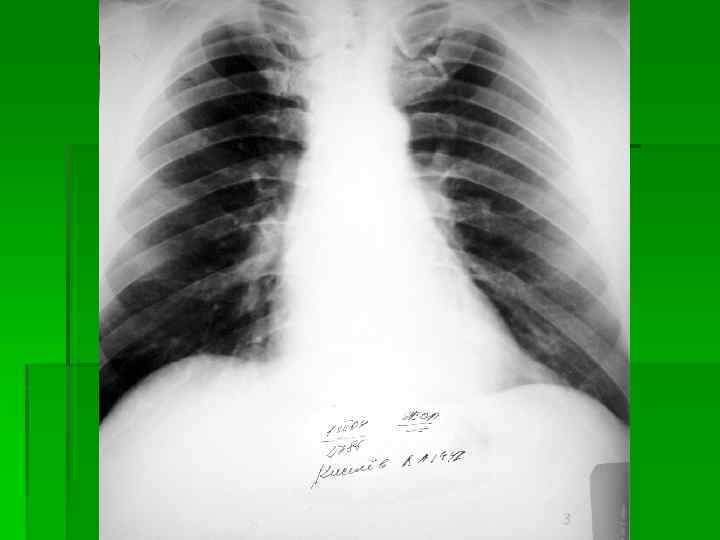

Рентгенологическая картина Малые затемнения Округлые (узелковоподобного типа) Обзорная рентгенограмма грудной клетки при узелковом пневмокониозе: видны многочисленные узелковые образования в средних и нижних поясах легких; корни легких расширены, тяжисты.

Рентгенологическая картина Малые затемнения Линейные (интерстициального типа) Обзорная рентгенограмма грудной клетки при интерстициальном пневмокониозе: отмечается сетчатая деформация легочного рисунка, видны многочисленные мелкие затенения, обусловленные перекрестом теней фиброзных тяжей; корни легких неструктурны; базальные отделы легких эмфизематозны.